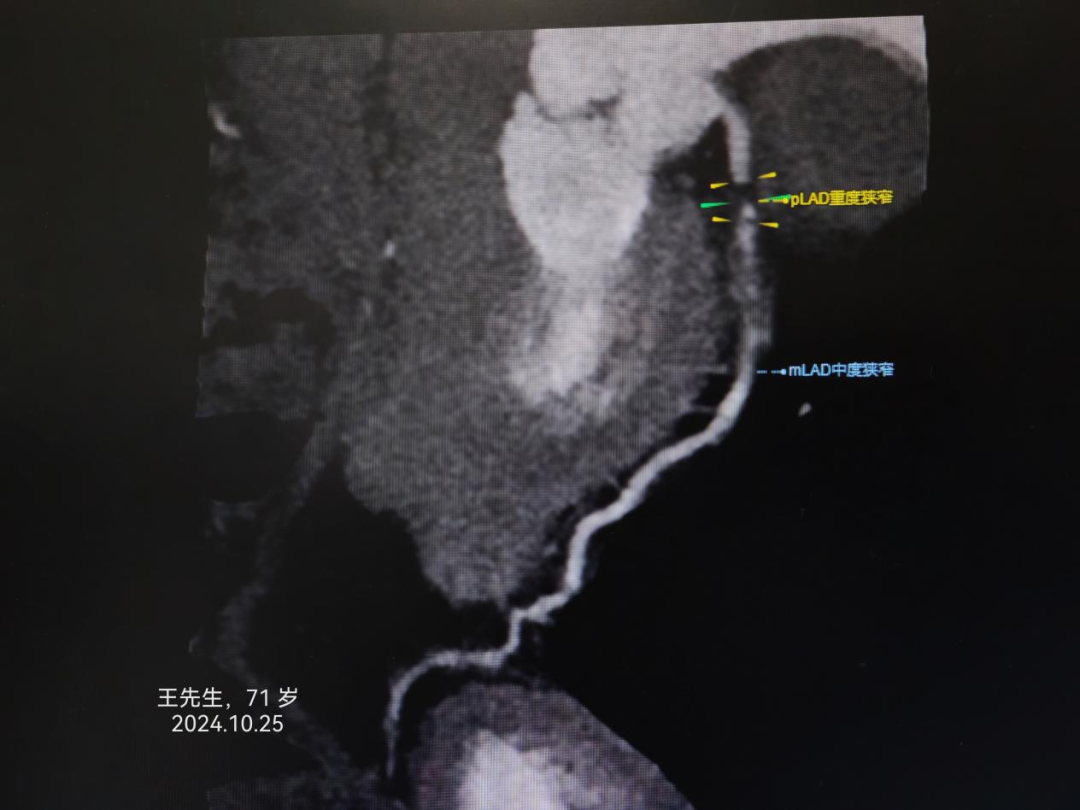

冠心病患者是猝死的高危人群。冠心病是中老年人最常见而且危害最大的心脏病之一,但随着生活节奏的加快和压力的增加,年轻人发病率也呈现增高的趋势。患者轻者可能无明显症状,但严重者可能会因此丧命。及时了解冠心病的早期症状对于早期发现和早期治疗有很大的帮助。